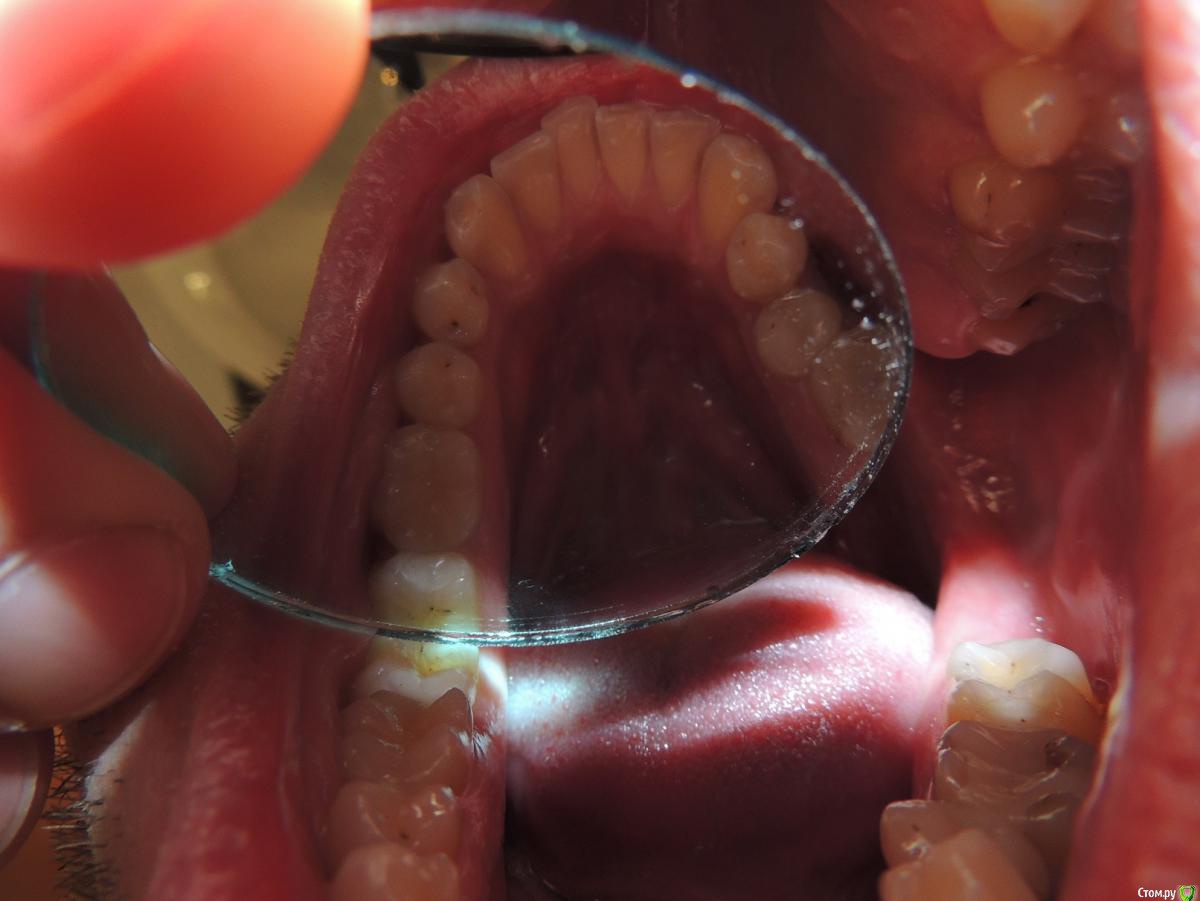

koct9ln Опубликовано 28 января, 2020 Поделиться Опубликовано 28 января, 2020 Господа хорошие, здравствуйте! Есть ли тут кто-нибудь, кто взялся бы дистанционно плотно изучить мою КТ и диагностировать наличие кариеса на зубах? Если вопрос в цене, то сколько бы это стоило? Мне нужна уверенность в диагностике, на которую я мог бы в дальнейшем опираться и возможно искать врача, который сумеет настолько же точно всё диагностировать, как это сделаете вы.Я думал, что увидеть кариес на КТ - плёвое дело: ищи тёмные структуры, не вписывающиеся в естественный вид зубов, пробрешину в эмали, и всё. Но либо это не так просто, либо мы с моим стоматологом небезосновательно расходимся во мнениях. А при попытках с гуглом научиться видеть кариес на КТ выплёвываются только статьи, рекламирующие клиники.Мне на днях полечили зуб 14, где был визуально диагностирован кариес с обоих сторон (в зеркало я видел лишь потемневшие фиссуры, коих у меня много). При этом диагностика делалась только визуально, без применения щупа или индикатора. Позже, у меня на руках появилось КТ, сделанное ДО лечения (изначально неудачно диск записался, потому не было возможности его показать врачу до лечения). И вот я никак не могу разглядеть на 14 никаких признаков кариеса, который подвергся лечению...На следующем приёме собираемся лечить кариес 44. Но опять же, сейчас гляжу КТ - не вижу там никакого кариеса. Хотя вот в зеркало вроде видно какую-то потемневшую область со стороны 5-ки...С помощью КТ можно ли ГАРАНТИРОВАННО увидеть наличие или ОТСУТСТВИЕ кариеса? Или же бывает такой кариес, который на КТ не видно, но видно непосредственно за зубе невооружённым глазом при личном осмотре?Прилагаю файлы с диска. Если надо, могу сканы каких нужно срезов накидать. И фотку зуба 44, который будет лечиться при следующем визите.(на всякий случай приложу ещё КТ 1.5-летней давности, если кто захочет глянуть в динамике).https://dropmefiles.com/c0ZHx- свежее КТ https://dropmefiles.com/G1Op2- КТ давность 1.5 года Ссылка на комментарий